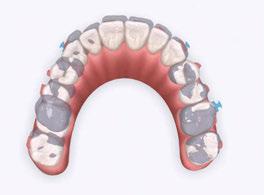

Maintain CL I occlusion. Develop the transverse relationships, eliminate the posterior negative root torques, and resolve the excessive gingival display via full-arch nonsurgical impaction. All vertical changes would be accomplished using only Angel Aligner, TADs, and elastics. Her maxillary lateral incisors may later require buildups to improve the Golden Proportion of the anterior teeth. My iOrtho software setup for maxillary intrusion was to place angelButtons (blue) between the U2s-3s, U4s-5s, and distal of the U6s (Figure 4).

Figure 4: My iOrtho virtual setup for Case 1. Note: This case was planned before virtual roots were available